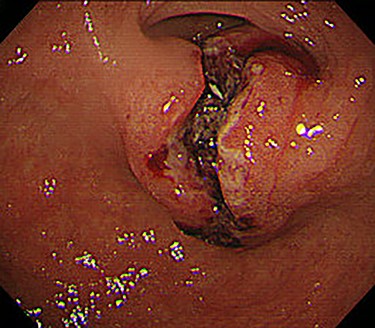

Chest and abdominal computed tomography (CT) showed no distant metastasis, but the tumor of the antrum was clearly visualized and was located close to the pancreatic head (Fig. 1). EGD revealed a large ulcerated lesion at the greater curvature of the antrum (Fig. 2). Hematoxylin and eosin staining of the biopsy specimen of the tumor confirmed a well-differentiated adenocarcinoma (tub1, tub2) (Fig. 3). The assessment of the HER2 expression by immunohistochemistry revealed the overexpression of HER2 (3+) in the biopsy tissue of the gastric tumor (Fig. 4).

EGD revealed a large ulcerated lesion at the greater curvature of the antrum.